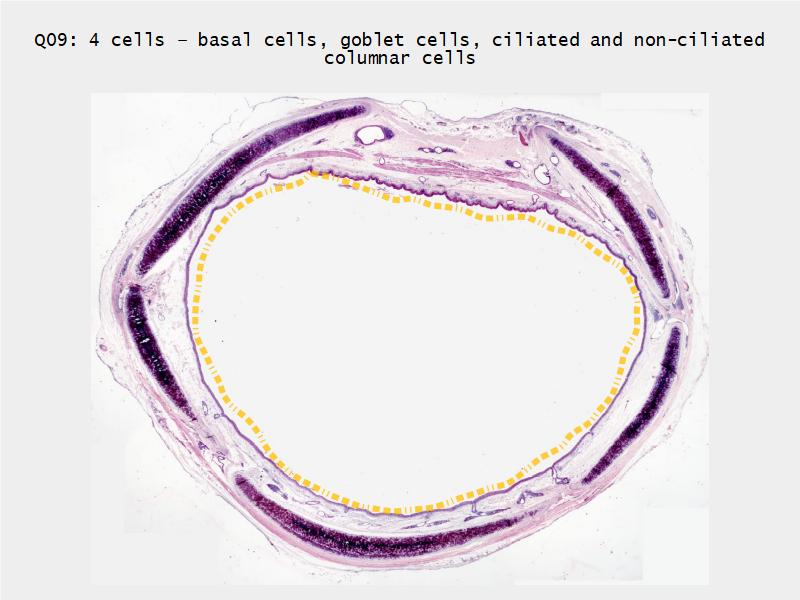

Respiratory Epithelium: Trachea

Respiratory epithelium

- Pseudostratified

- Ciliated

- Columnar

- Epithelium with

- 4 Cells

- Ciliated columnar cells

- Non-ciliated columnar cells

- Goblet cells

- Basal cells